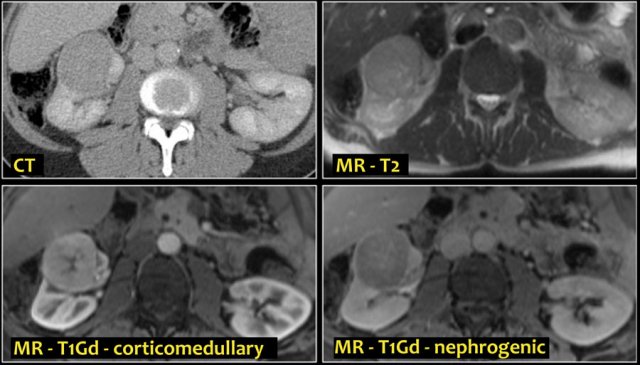

A typical feature of clear cell carcinoma is strong enhancement in the corticomedullary phase.

This can be difficult to assess when the lesion is small and located in the renal cortex, which also enhances strongly.

The nephrogenic phase is therefore the most sensitive phase for the detection of these lesions, as the renal parenchyma enhances homogeneously and more intensely than the tumor (figure).

On MR clear cell RCC is usually iso- to hypointense on T1 and hyperintense on T2-weighted images.

Typically renal cell carcinomas do not have extracellular fat, which differentiates them from angiomyolipomas.

However 80% of clear cell RCC have intracellular fat, which leads to a drop in signal intensity on T1 opposed-phase images compared to in-phase images.

The corticomedullary phase 25-40 sec post injection is strongly recommended. It helps to differentiate tumor from pseudotumor and to assess enhancement of a lesion.

In this phase however a tumor located in the renal medulla can have the same attenuation as the surrounding parenchyma (figure).

Therefore the nephrogenic phase (±100 sec post injection) is the most important phase for the detection of a tumor.